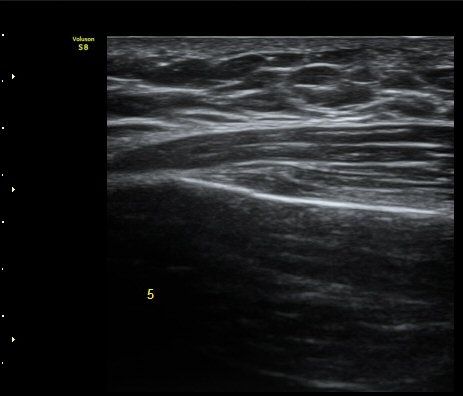

ÃÊÀ½ÆÄ °Ë»ç

¹Ì¼¼ÇÏ°Ô °¥ºñ»À ÇÇÁú°ñ ¿¬°á¼º ¼Ò½Ç°ú ¿¬ºÎÁ¶Á÷ ºÎÁ¾ÀÌ °üÂûµÊ(loss of cortical continuity and soft tissue swellingof rib)   »çÁø 1, 2, 3

3, 4,, 5 ¹øÂ° °¥ºñ»À °ñÀýÀÌ È®ÀεÊ.